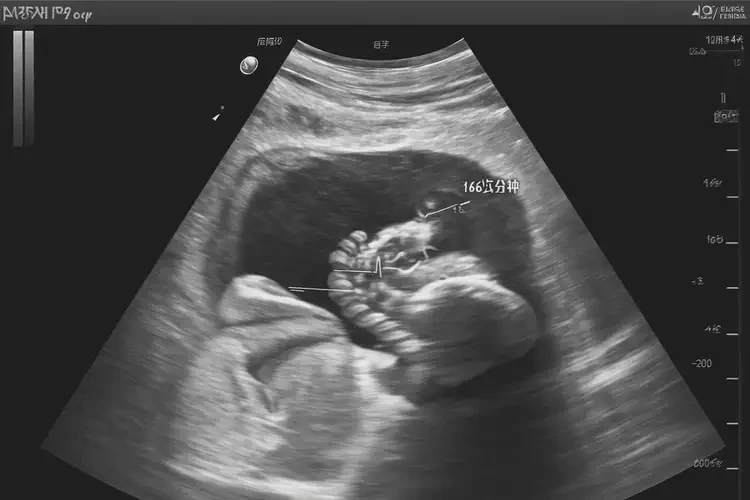

孕12周4天胎心166怎么回事

166次/分鐘

孕12周4天時,胎兒的胎心率在166次/分鐘,這屬于正常范圍。胎心率是指胎兒心臟每分鐘跳動的次數(shù),通常在孕早期(12周前)胎心率較快,可達(dá)到160-180次/分鐘。隨著孕周增加,胎心率會逐漸下降,到孕晚期(36周后)通常在120-160次/分鐘。

孕12周4天胎心166怎么回事(圖1)